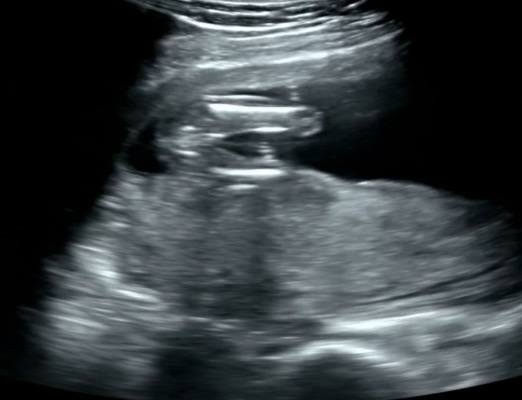

기형아2차 검사&성별 확인

오늘 16주3일차 기형아2차 검사하고 왔어요 아기가 엄청 컸네요 ㅎㅎ 신통방통 오늘은 성별까지 확인하고 왔어요 가랑이 사이가 뭐가 없다고 ㅋㅋㅋ 의사선생님께서 힌트를 주셨는데 없다가 생기는 반전은 없겠죠? 남편이랑 저랑 딸을 바랬는데 너무 기뻐요!!

축하드려용ㅋㅋ딸에서 아들은 20주까지는 반전이 있을 수 있단 얘기가 있기하던데 초음파사진상으론 매끈해보이네용😊